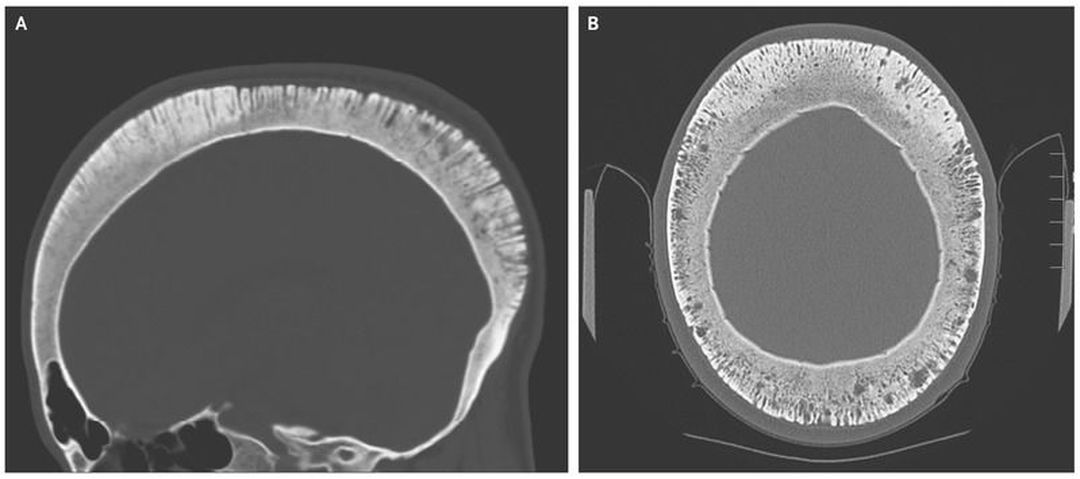

A 35-year-old man with a history of sickle cell disease presented with a sickle cell crisis and headaches. Noncontrast computed tomography (CT) of the head revealed a thickened calvaria with perpendicular proliferation of the trabeculae, a finding termed the hair-on-end sign (Panels A and B). The hair-on-end sign was historically described on plain films (although it can also be seen on CT and magnetic resonance imaging) in patients with severe anemias, primarily thalassemia major and, less commonly, sickle cell disease. It has more rarely been described in patients with hemolytic anemia, spherocytosis, chronic iron deficiency, or cyanotic congenital heart disease. The appearance is due to anemia causing red marrow proliferation and a widened diploic space with thinning of the outer table of the skull. Destruction of the vertical trabeculae occurs in conjunction with thickening of the residual trabeculae. When the outer table is disrupted, new spicules also form, which results in this alternating pattern of new spicules amid nonradioopaque marrow. The patient’s headache resolved quickly in response to treatment with pain medication and did not recur during his hospital stay.